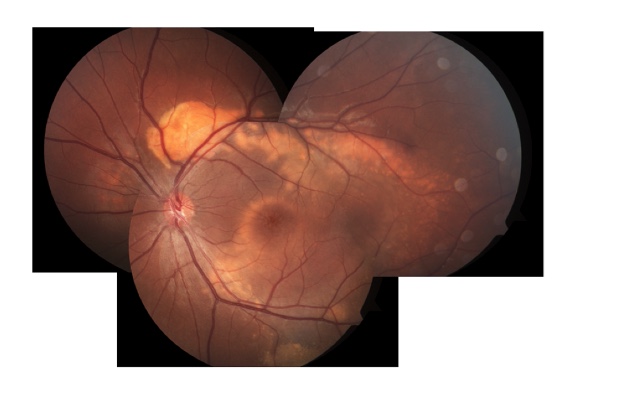

Discovery and Description of Retinal Angiomatous Proliferation, a Form of Neovascularized Age-Related Macular Degeneration

Retinal angiomatous proliferation was a major accomplishment supported by The Macula Foundation, which Identified neovascularization which originated in the retina and became known eventually as Type 3 neovascularization in age-related macular degeneration. Also, it was referred to as Retinal Angiomatous Proliferation or RAP.

Yannuzzi LA, Negrao S, Iida T,Carvalho C, Rodriguez-Coleman H, Slakter JS, Freund KB, Sorenson J, Orlock D, Borodoker N.

Retinal angiomatous proliferation in age-related macular degeneration.RETINA 21:416-434, 2001.